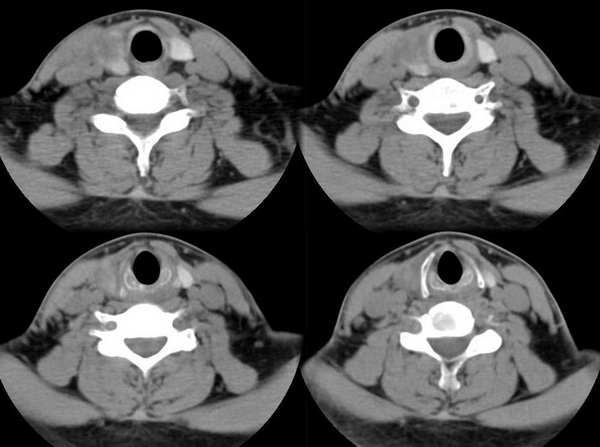

男,25岁,体温39.3度,发现右侧颈部包块.

会不会是甲状腺脓肿

肿块还是有强化的,会不会是甲状腺癌呢?但是体温39.3度不好解释,等待高手发言

支持脓肿!!!

此病例特点:1、年轻男性,基本上是高热;2、右侧甲状腺肿大呈边界不清之低密度,但甲状腺境界清晰;3、基本没有增强但低密度的周边略呈边缘增强反应;4、最好补充病史:痛否?时间?(如痛、急性起病。)

据此,以甲状腺急性炎症可能性大。

甲状腺脓肿